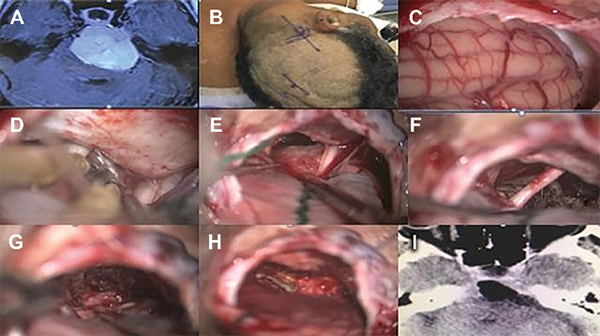

Figura 6: Meningioma petroclival del clivus superior y medio sin extensión de la fosa media. (A) Se seleccionó el abordaje retrosigmoideo para este caso, con el paciente posicionado en decúbito lateral (Park Bench) (2). La craneotomía o craniectomía con reconstrucción con cemento óseo se debe realizar exponiendo parte del seno sigmoideo y transversal. Con eso, la apertura de la duramadre.

Figura 7: Meningioma petroclival grande resecado por abordaje suboccipital. Se observa un pequeño componente tumoral que se extiende en la fosa media en continuidad con el tentorio. Esta parte tumoral se resecó abriendo el tentorio a través de la fosa posterior. No se resecó una pequeña extensión en el seno cavernoso.